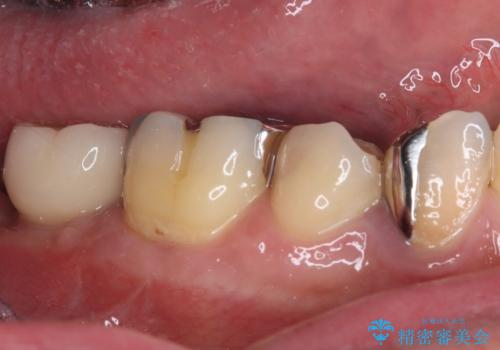

- 下顎左右の奥歯を治療途中で放置してしまっているとのことで来院された患者様です。

欠損部はインプラントによる補綴治療を、土台の外れてしまった歯は、根管治療を行った上で、補綴治療を行うこととしました。